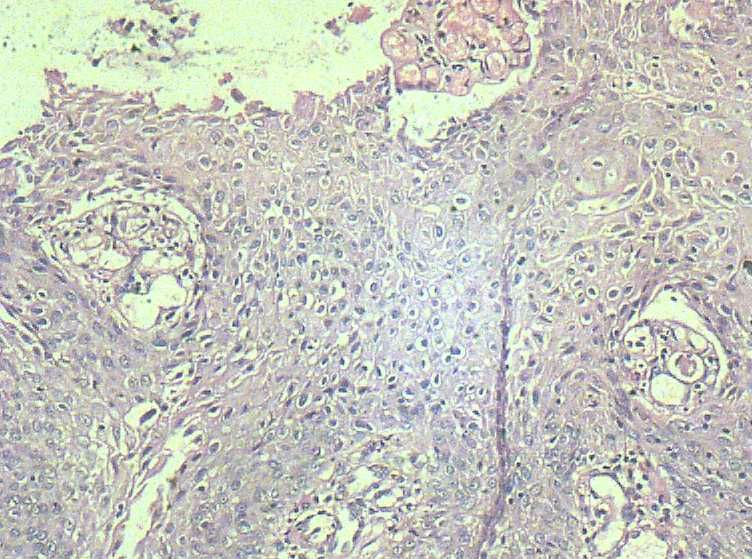

33岁 宫颈刮片看上去很像腺上皮病变,报了AGC 建议活检。 活检取自宫颈,图片如下:请帮忙看下,谢谢!

鳞状上皮增厚,乳头状增生,并见挖空样细胞。提示HPV感染。

有不典型增生, 不知道大家有没有看到。  如果有不典型和上面的图像可或直接报 :尖锐湿疣伴不典型增生。